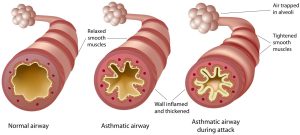

2.अस्थमा

अस्थमा वायु मार्ग प्रभावित करता है |

तेज ठंडी गांड छाती में वायु मार्ग शक्ति हो जाता है जिससे सांस लेना मुश्किल हो जाता है अस्थमा पीठ दर्द भी हवा के लिए मुंह से सांस लेना शुरू कर देते हैं परिणाम स्वरुप स्वस्थ हवा सांस के माध्यम से फेफड़े प्रवेश करने लगती है जिससे वायु मार्ग में इन्फ्लेमेशन होने लगता है

उपाय – डायाफ्राम ब्रीदिंग फायदेमंद है

घुटनो को मोड़कर पीठ के बल लेट जाएं नाक से धीरे-धीरे सांस ले हवा को पेट में गहराई तक अंदर जाने दे पेट फूलना चाहिए | अब होठों को सिकुड़ कर सांस छोड़ और पेट को अंदर की ओर जाने दे इसी दौरान दवाई जरूर समय पर ले |